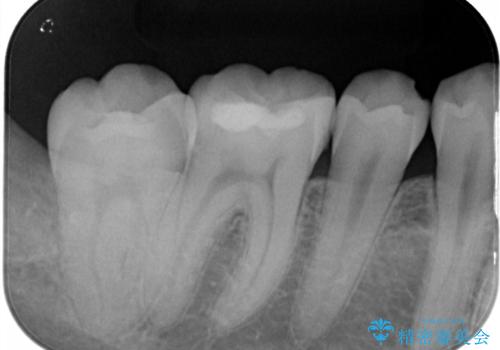

- 他院で行った、古いセラミックが欠けたとのことでご来院された患者様です。

古いセラミックを外すと、無数のヒビが入っており、そこからできた新しい虫歯がありました。

古い材料も虫歯もすべて除去して、根本からやりかえました。

セラミックが欠けるほど強い力がかかっているということは、ご自身の歯も割れている(小さいヒビ等も含む)可能性があります。拡大鏡でしっかり見ながら治療します。

咬む力が強いため、このままでは何度もセラミックとご自身の歯を割る可能性就寝時マウスピースの使用をご提案しました。患者様には、大変満足して頂きました。